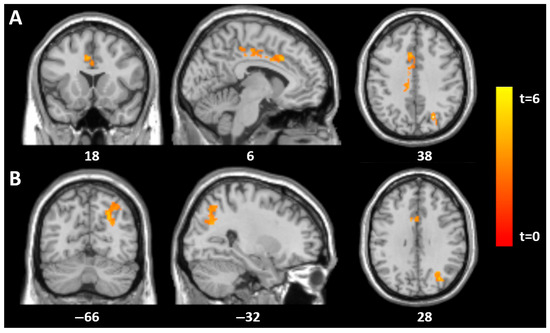

| SCID total | |||||||

| Mid-cingulate | 1062 | 6 | −18 | 48 | 6.1 | <0.001 | 0.01 |

| −9 | 2 | 51 | 4 | ||||

| Left superior parieto-occipital | 657 | −27 | −60 | 48 | 4.2 | 0.01 | 0.01 |

| Histrionic | |||||||

| Mid-cingulate | 1111 | 3 | −18 | 44 | 8.8 | <0.001 | 0.01 |

| −3 | −6 | 48 | 6.1 | ||||

| Thalamus | 6478 | −5 | −11 | 15 | 7.1 | 0.001 | |

| Left superior parieto-occipital | 1165 | −30 | −68 | 54 | 7.7 | <0.001 | |

| Right angular gyrus | 909 | 42 | −74 | 36 | 6.2 | 0.001 | |

| Borderline | |||||||

| Right mid-cingulate | 570 | 14 | −21 | 45 | 5.4 | 0.027 | 0.01 |

| Antisocial | |||||||

| Right mid-cingulate | 501 | 5 | −20 | 42 | 4.4 | 0.05 | 0.01 |